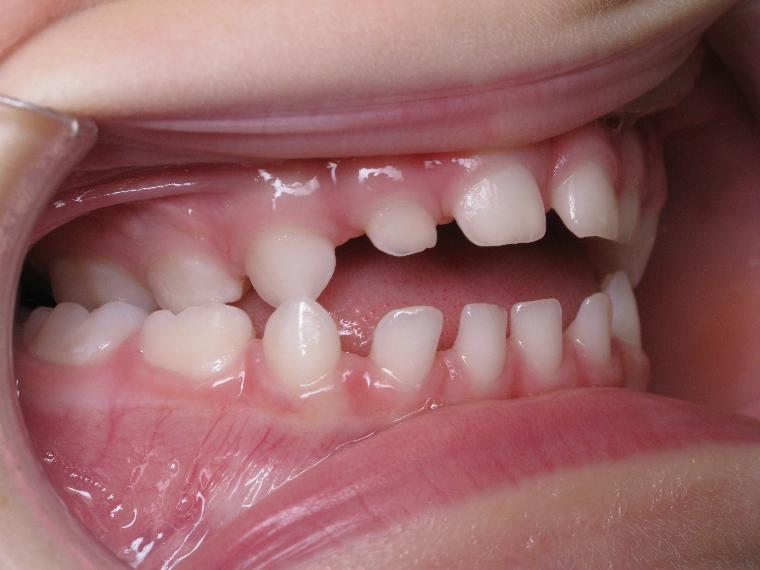

12 béance inversé droit 4 ans

inversion postérieur coté droit et espace entre les dents du haut et du bas (diastèmes)